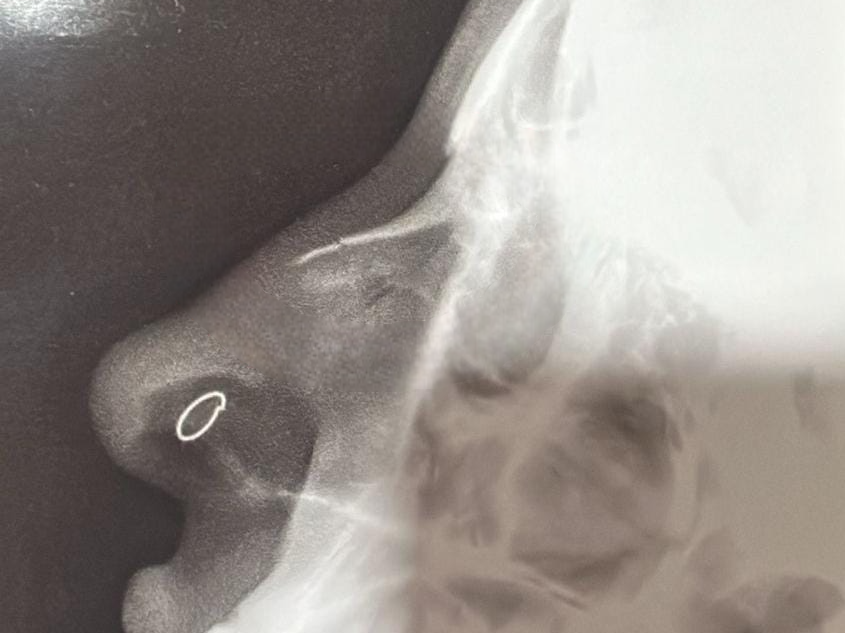

Após a agressão, a mulher procurou atendimento médico em um pronto-socorro particular na região central da cidade e, posteriormente, compareceu ao plantão policial, onde formalizou a denúncia. Uma cópia da radiografia, que aponta fratura, foi anexada à queixa.